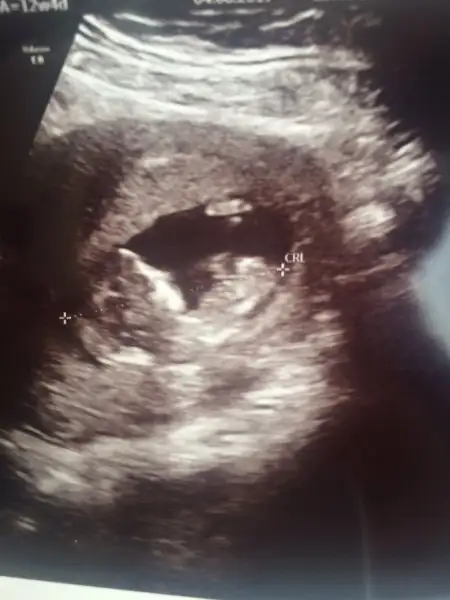

Çok geçmiş olsun canım.Neden darmış yeri, rahimde perde filan mı vardı acaba?İyi pazarlar güzel anneler ,cumadan beri herşeye ağlıyorum yazmıştım ogün doktora gittik su az yeri dar dedi ama kafana takma dinlen haftaya bakacağım dedi elimde değil kafaya takmamak bide elim durmuyor sürekli bişeyler okuyorum amniyon sıvısı bebeğin idrarıymış acaba böbrekte mi sorun var diyorum idrarını mı yapamıyor acaba ama haftasıyla uyumlu kendimi rahatlatmaya çalışıyorum ama olmuyor dua edip namaz falan kıldıkça daha çok ağlıyorum burdan arkadaşlar havuç suyu iç dedi üç gündür içiyorum dua edip duruyorum size fotosunu atayım o siyah yerler suymuş miktarını da sormayı unuttum o şaşkınlıkla işte böyle kızlar oğluşum iyidir inşallah

Havuç suyu amniyo sıvısını arttırıyor iç tatlım dua edicem senin için inş düzelir aglama ne olurİyi pazarlar güzel anneler ,cumadan beri herşeye ağlıyorum yazmıştım ogün doktora gittik su az yeri dar dedi ama kafana takma dinlen haftaya bakacağım dedi elimde değil kafaya takmamak bide elim durmuyor sürekli bişeyler okuyorum amniyon sıvısı bebeğin idrarıymış acaba böbrekte mi sorun var diyorum idrarını mı yapamıyor acaba ama haftasıyla uyumlu kendimi rahatlatmaya çalışıyorum ama olmuyor dua edip namaz falan kıldıkça daha çok ağlıyorum burdan arkadaşlar havuç suyu iç dedi üç gündür içiyorum dua edip duruyorum size fotosunu atayım o siyah yerler suymuş miktarını da sormayı unuttum o şaşkınlıkla işte böyle kızlar oğluşum iyidir inşallah